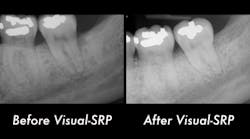

A clinical periodontal and radiographic assessment is completed. Although there is moderate bone loss in all four quadrants, his periodontal status is stable with the exceptions of Nos. 18 and 31 distal (figures 1 and 2). Both areas reveal direct distal probing depths of at least 10 mm and radiographic infrabony distal defects.

Figure 1: No. 18

Figure 2: No. 31